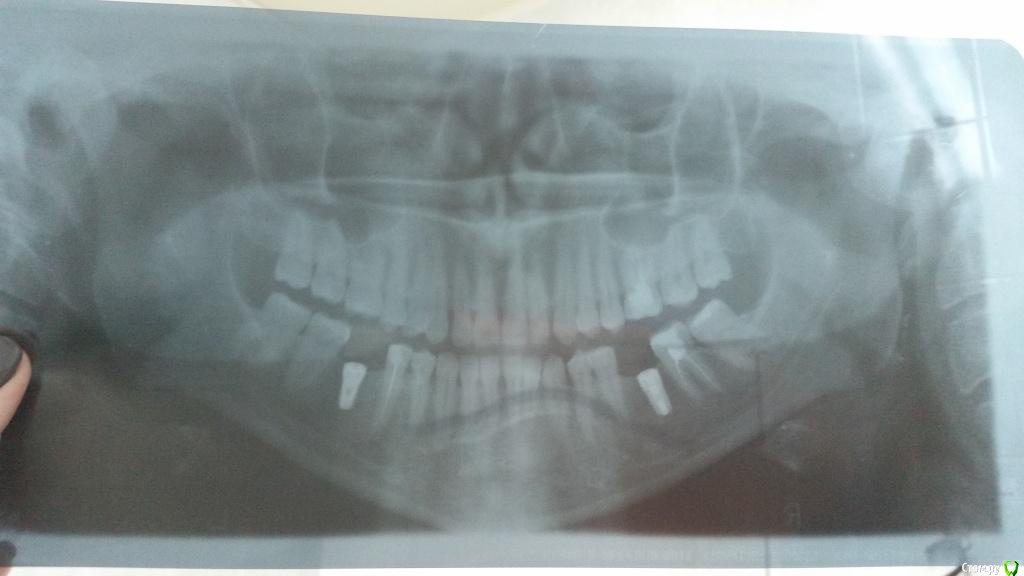

Валерия2020 Опубликовано 3 декабря, 2016 Поделиться Опубликовано 3 декабря, 2016 Прошла неделя после снятия швов. Десна до конца не срослась, виднеется зеленая заглушка.Переживаю что это ворота для инфекции. Постоянно пользуюсь хлоргексидином, холисалом, солкосерил дентальный. Хорошо прополаскиваю - и после этого края десны будто раздвигаются и заглушка видна еще больше. Что мне делать в такой ситуации? Как уберечь себя от воспаления? И можно ли в таком состоянии доходить 3 месяца до установки формирователя. Спасибо. (на фото десна после ночи с солкосерилом, к вечеру она сильнее расходится) Ссылка на комментарий

Валерия2020 Опубликовано 22 января, 2017 Автор Поделиться Опубликовано 22 января, 2017 все же надо было тогда формирователь ставить. Пластика десны нужна.Проблемы с несросшейся десной были справа. Потом я выкладывала апдейт, что всё нормализовалось. А сейчас начались проблемы с десной слева (мне установили 2 импланта), изначально проблем слева вообще не было.Кстати на орто видно, что левый имплант стоит выше правого относительно кости. Ссылка на комментарий